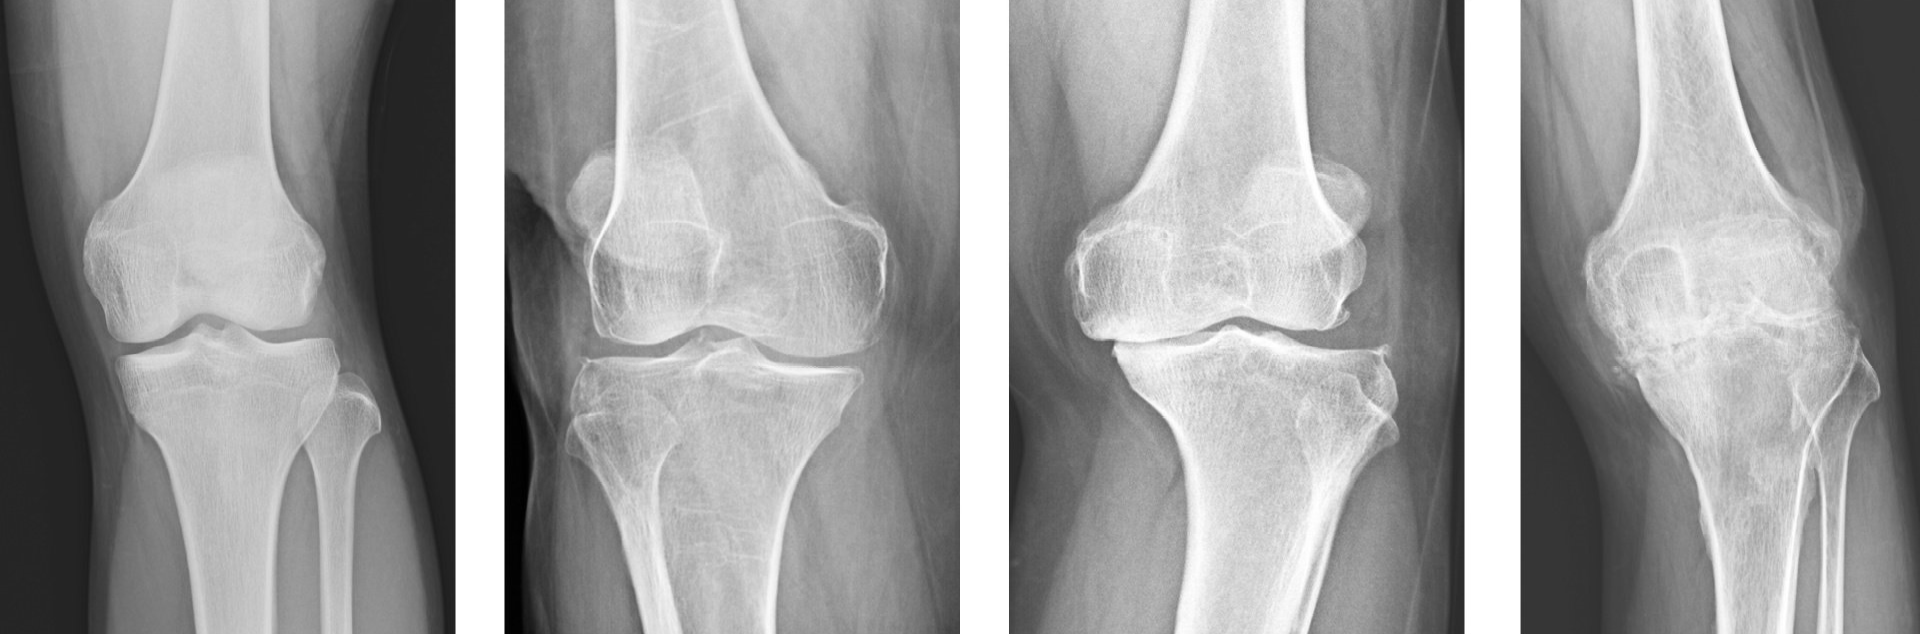

- Ακτινογραφίες:

- Φας και προφίλ

- Οι ακτινογραφίες λαμβάνονται για να επιβεβαιώσουν τη διάγνωση και πρέπει να είναι σε ορθία θέση, έτσι ώστε να ανιχνεύεται καλύτερα ο βαθμός στένωσης του μεσάρθριου διαστήματος που είναι ένα από τα βασικά χαρακτηριστικά της οστεοαρθρίτιδας